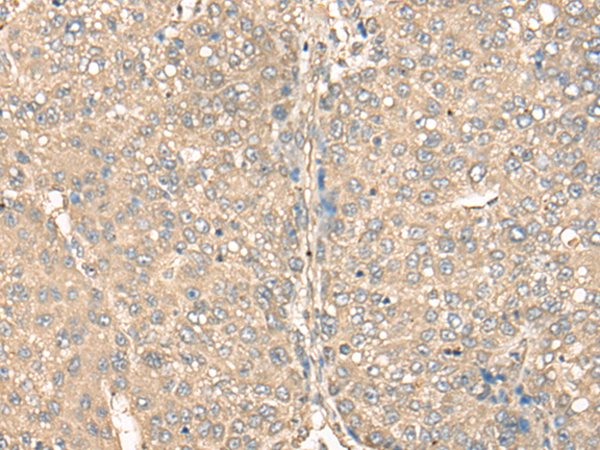

IHC positive control: |

Human liver cancer and human brain |

IHC Recommend dilution: |

25-100 |